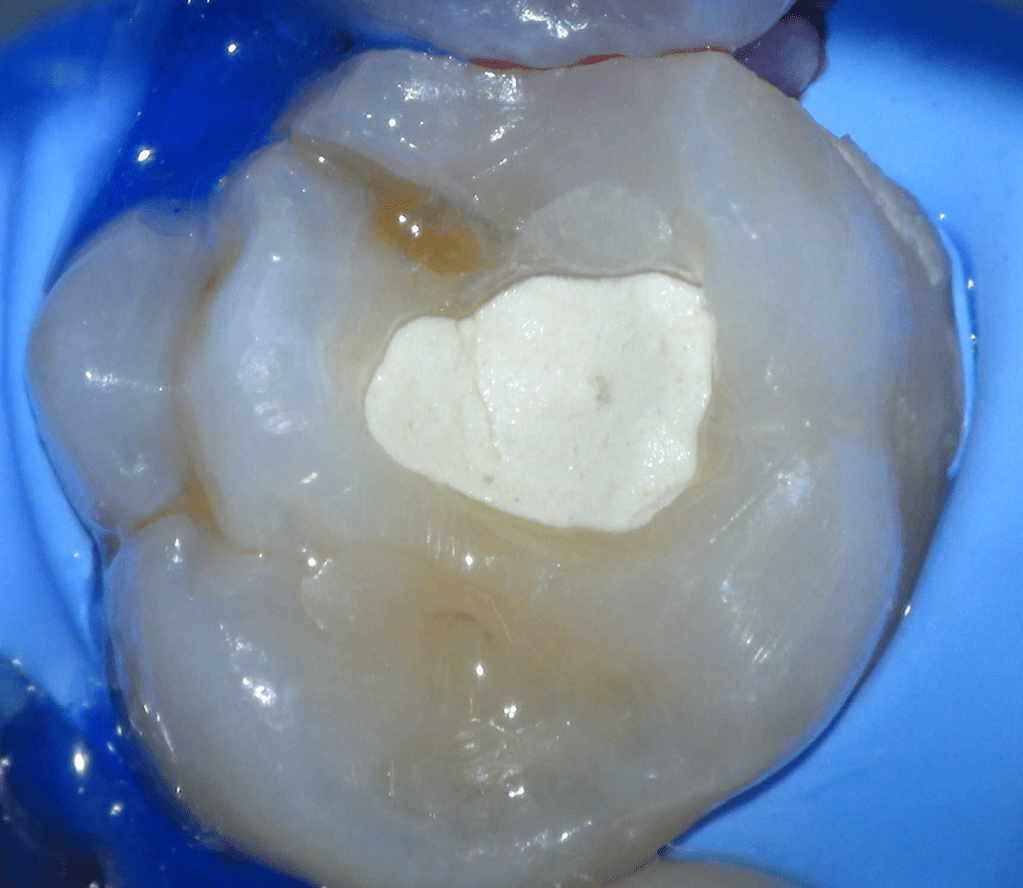

Reconstrucción preendodóntica